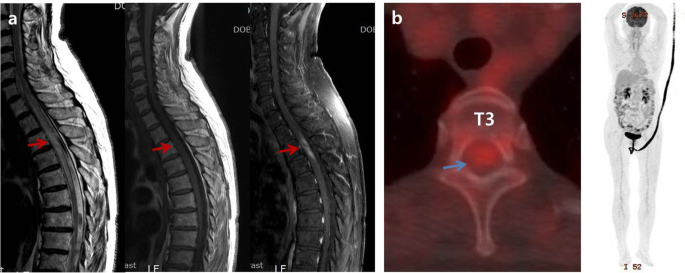

A 75-year-old female patient presented with sudden-onset flaccid paraparesis for 1 day. The patient had a history of diabetes and hypertension. Neurological examination showed grade 2–3 motor weakness of both legs, decreased deep tendon reflex, loss of anal tone, and numbness below the T4 dermatome. There was no fever, cardiopulmonary symptoms, pain of extremities, or palpable lymph nodes. Magnetic resonance imaging (MRI) revealed an intramedullary mass lesion on T2-T4 with cord swelling and edema from C7 to T6. The lesion was iso-intense on T2-weighted images (WI) and iso- to slightly low-intense on T1-WI with heterogeneous enhancement (Fig. 1a). No additional lesions were found on the brain and whole-spine MRI. Whole-body 18F-fluorodeoxyglucose positron emission tomography/computed tomography (FDG-PET/CT) confirmed the single lesion on T2-4 with a maximum standardized uptake value (SUVmax) of 3.14 and no systemic lesion (Fig. 1b). Leg weakness deteriorated to G1 prior to surgery.

Preoperative magnetic resonance imaging shows intramedullary mass lesion with iso-intense on T2-weighted images (WI) and iso- to slightly low-intense on T1-WI on T2-4, which was heterogeneous enhanced pattern with cord swelling and edema from C7 to T6 (red arrows) (a). There was a single lesion on T2-4 with maximum standardized uptake value (SUVmax) of 3.14 and no systemic lesion on whole-body 18F-fluorodeoxyglucose positron emission tomography/computed tomography (blue arrow) (b)